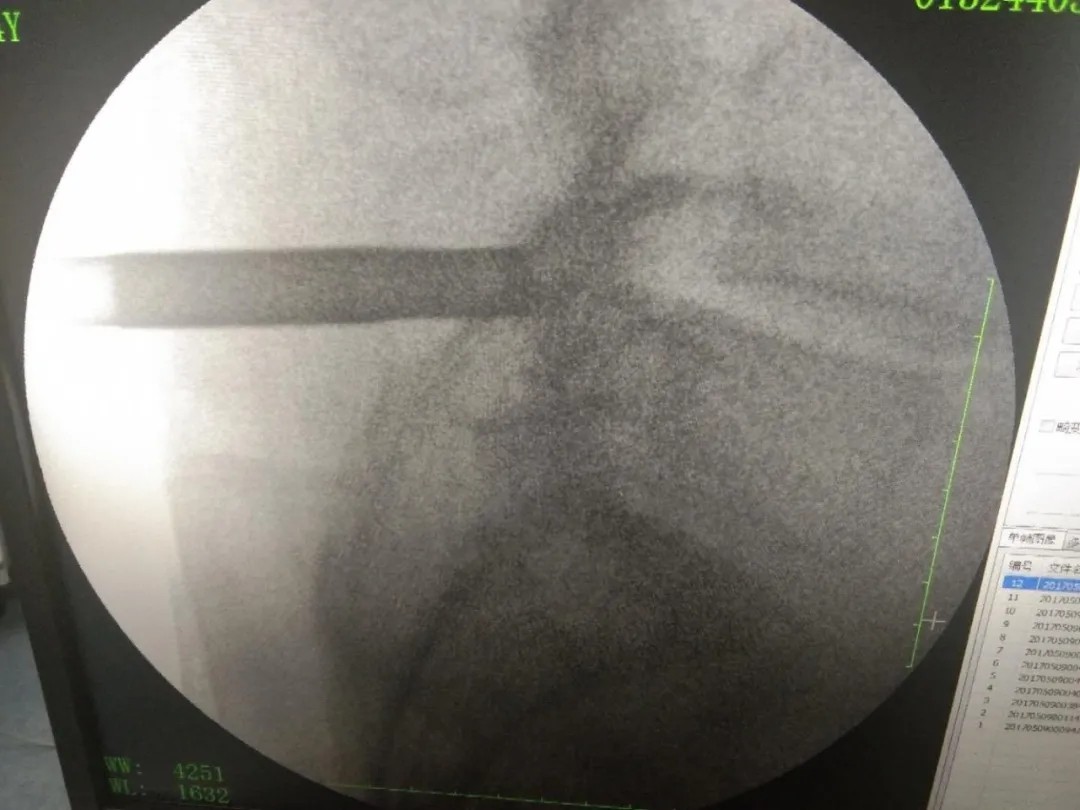

术后影像:

椎间孔镜技术,是一种方兴未艾的微创手术方法,在治疗椎间盘突出、腰椎管狭窄症等治疗中常见常用。于治强主任这两个病例采用椎间孔镜技术治疗,取得相当不错的疗效。